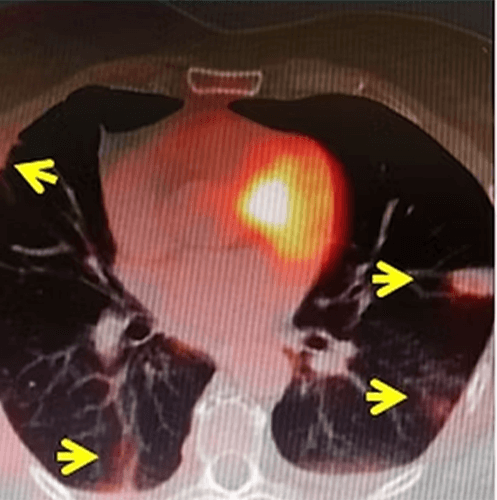

In our patient who had 9 colon cancer metastases (arrows) in his lung, all the masses were cryoablated. Three months later, the control PET-CT showed disappearance of tumor activity (arrows).

Colorectal cancers can also metastasize to other organs, including the lungs, besides the liver. Lung metastases can be treated or locally controlled by percutaneous ablation methods, such as radiofrequency, microwave, and cryoablation, if their number and size are favorable.